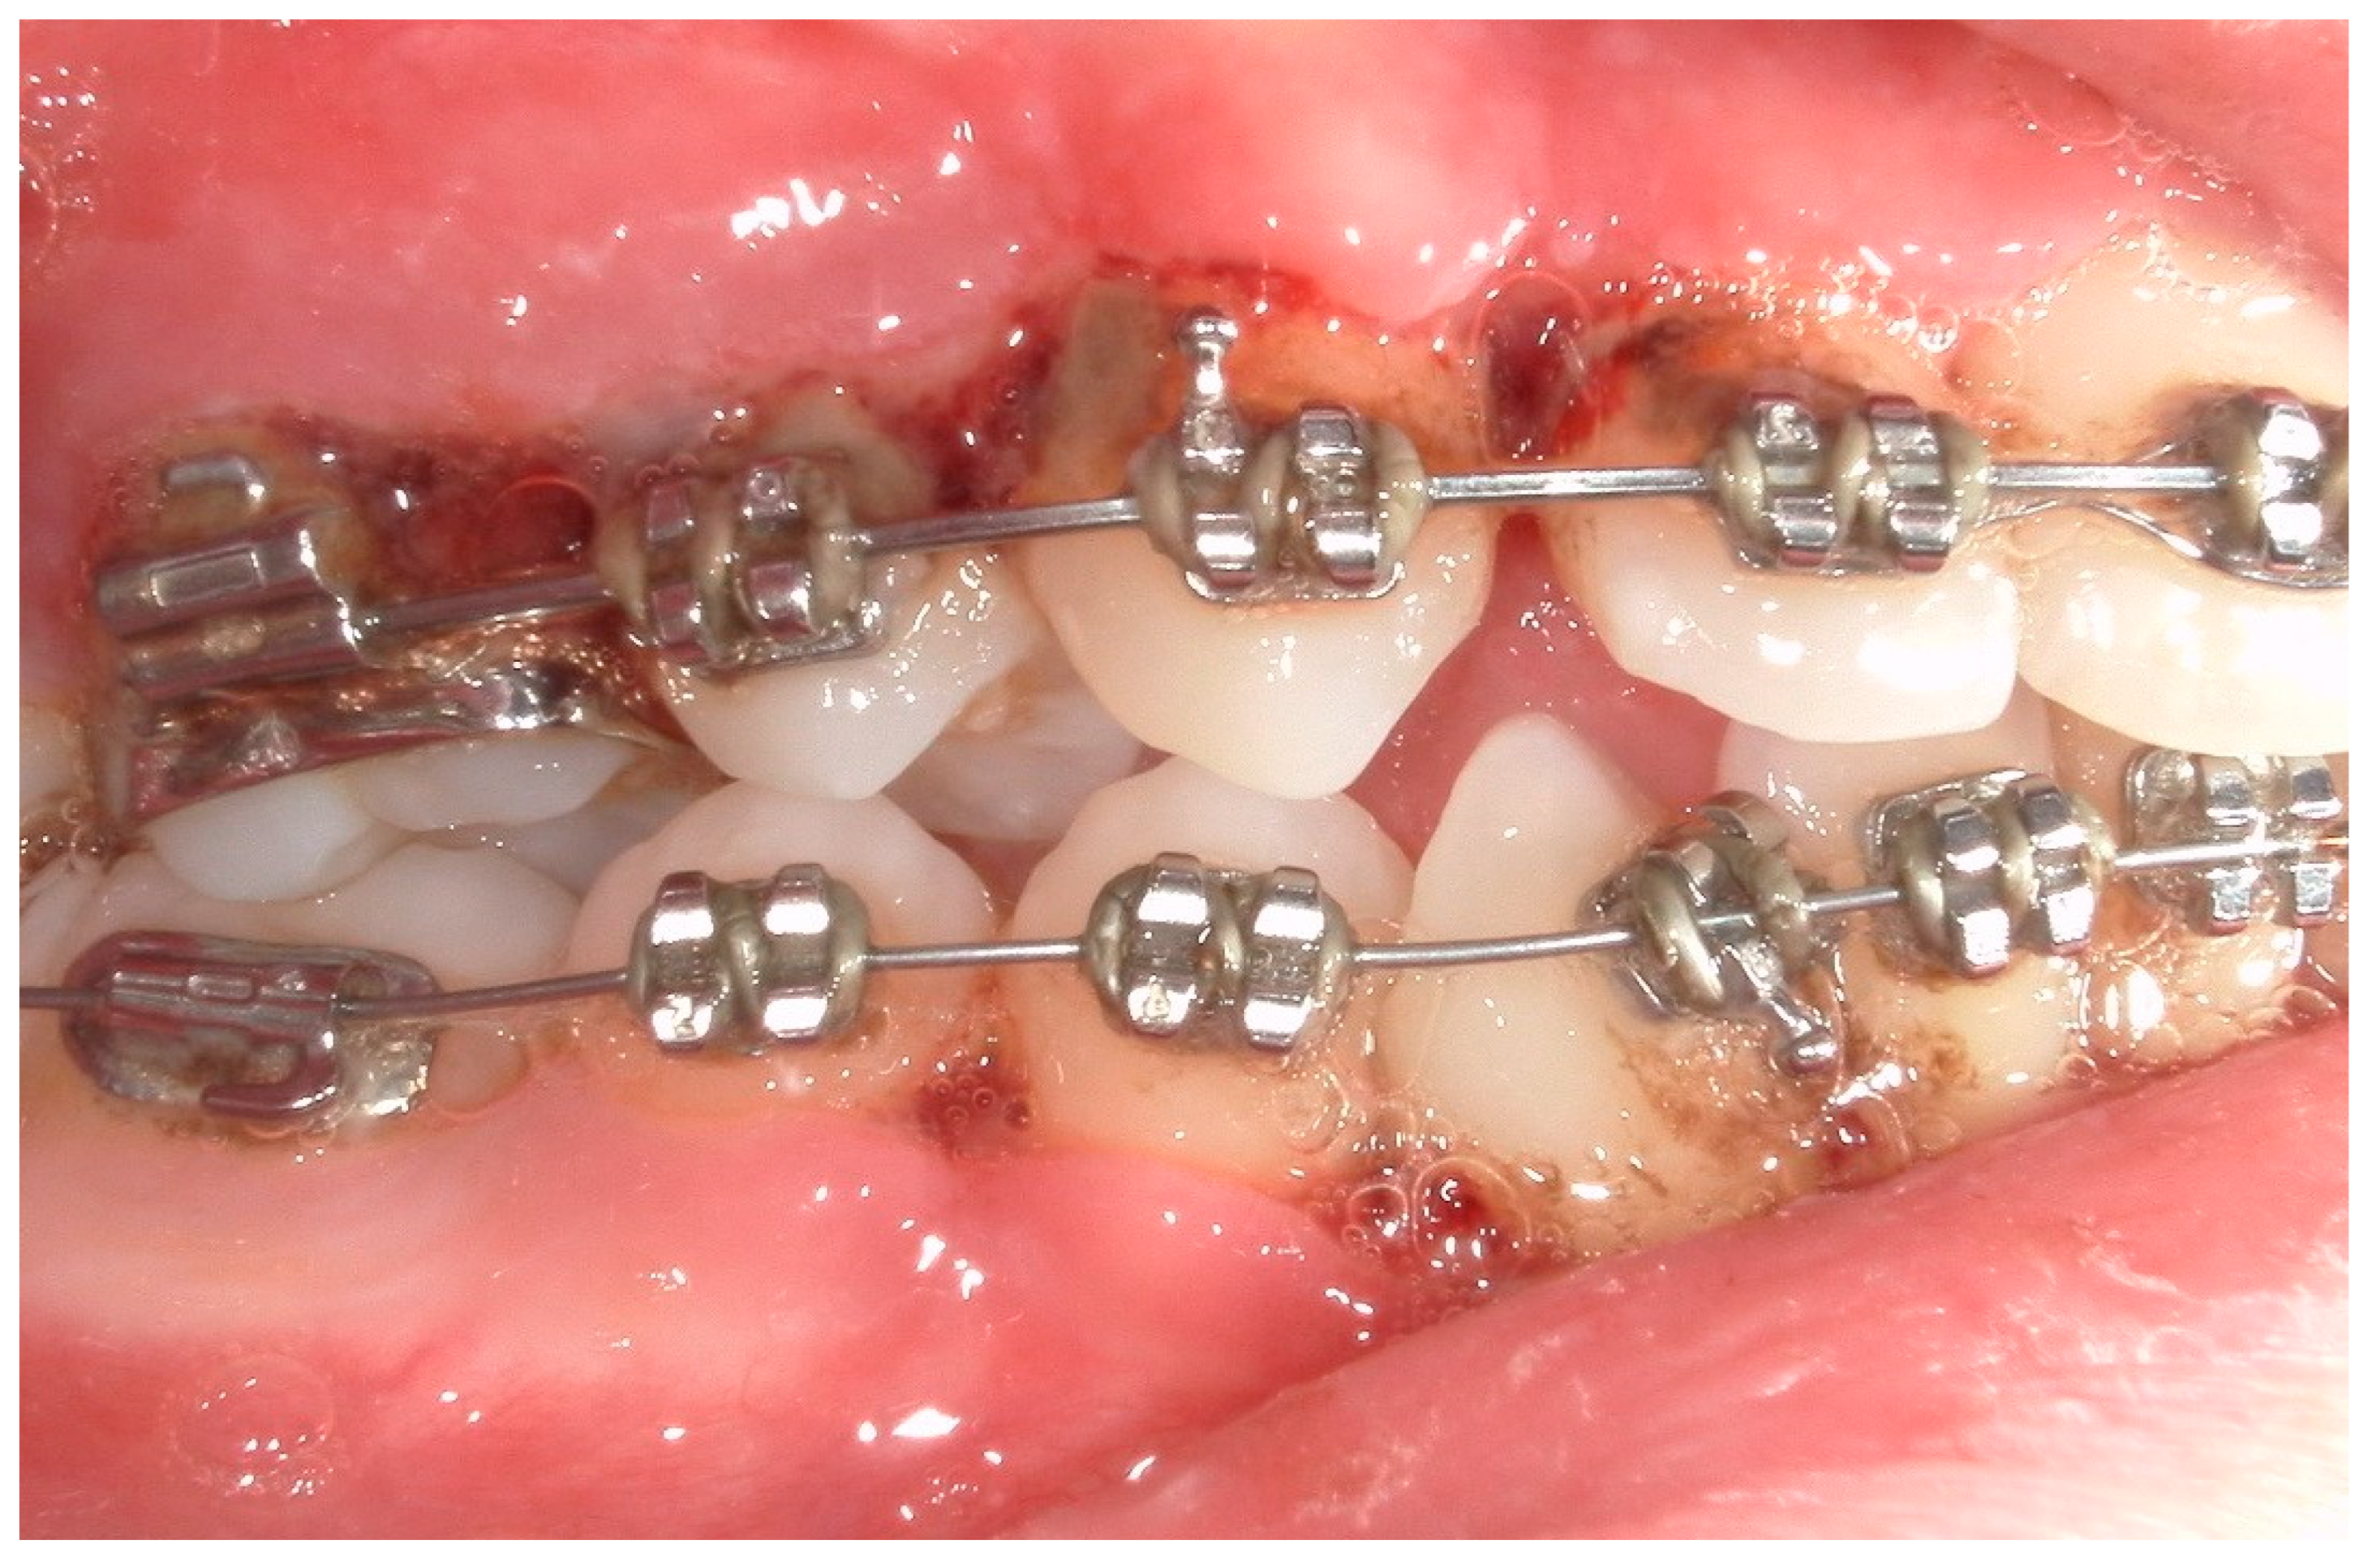

4.1. Case 1

4.2. Case 2